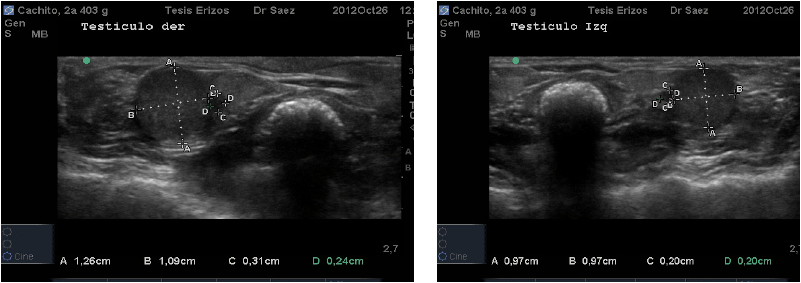

Topográficamente los testículos de los ETA se encuentran intra abdominales, vía ecográfica se observan caudo-ventralmente en el abdomen caudal y ubicados dentro de los recesos para-anales. El órgano presentó forma circular en el corte transverso, en la parte media, a diferencia del corte longitudinal donde se observaron ovalados. Su eje largo presentó una ligera oblicuidad siendo dorso-craneal/caudo-ventral. Su parénquima se presentó de mediana ecogenicidad, granulado fino y homogéneo. No se visualizó la línea ecogénica que describió Nyland [7] en el interior del testículo de animales domésticos, que correspondería al mediastino testicular (FIG. 4), esto podría deberse a que probablemente el mediastino en esta especie es menos fibroso o podría ser menos desarrollado y ubicarse en el extremo craneal del testículo, tal como ocurre en el equino (Equus caballus). Sería recomendable realizar un estudio morfoestructural para confirmar esta observación.

Los resultados cuantitativos de morfometría fueron medidos en centímetros (cm) y expresados en promedios junto con desviación estándar (X ± DE). Se midió ancho, alto y largo de Testículo Izquierdo, y Testículo Derecho. En el caso del Epidídimo se midió ancho y alto de epidídimo en diez machos, ya que en uno de los pacientes no fue observable. En el 80% de los casos en el epidídimo predominó el ancho sobre el largo. Se midió el ancho, alto y largo de la Próstata. Los resultados se especifican en la TABLA III.